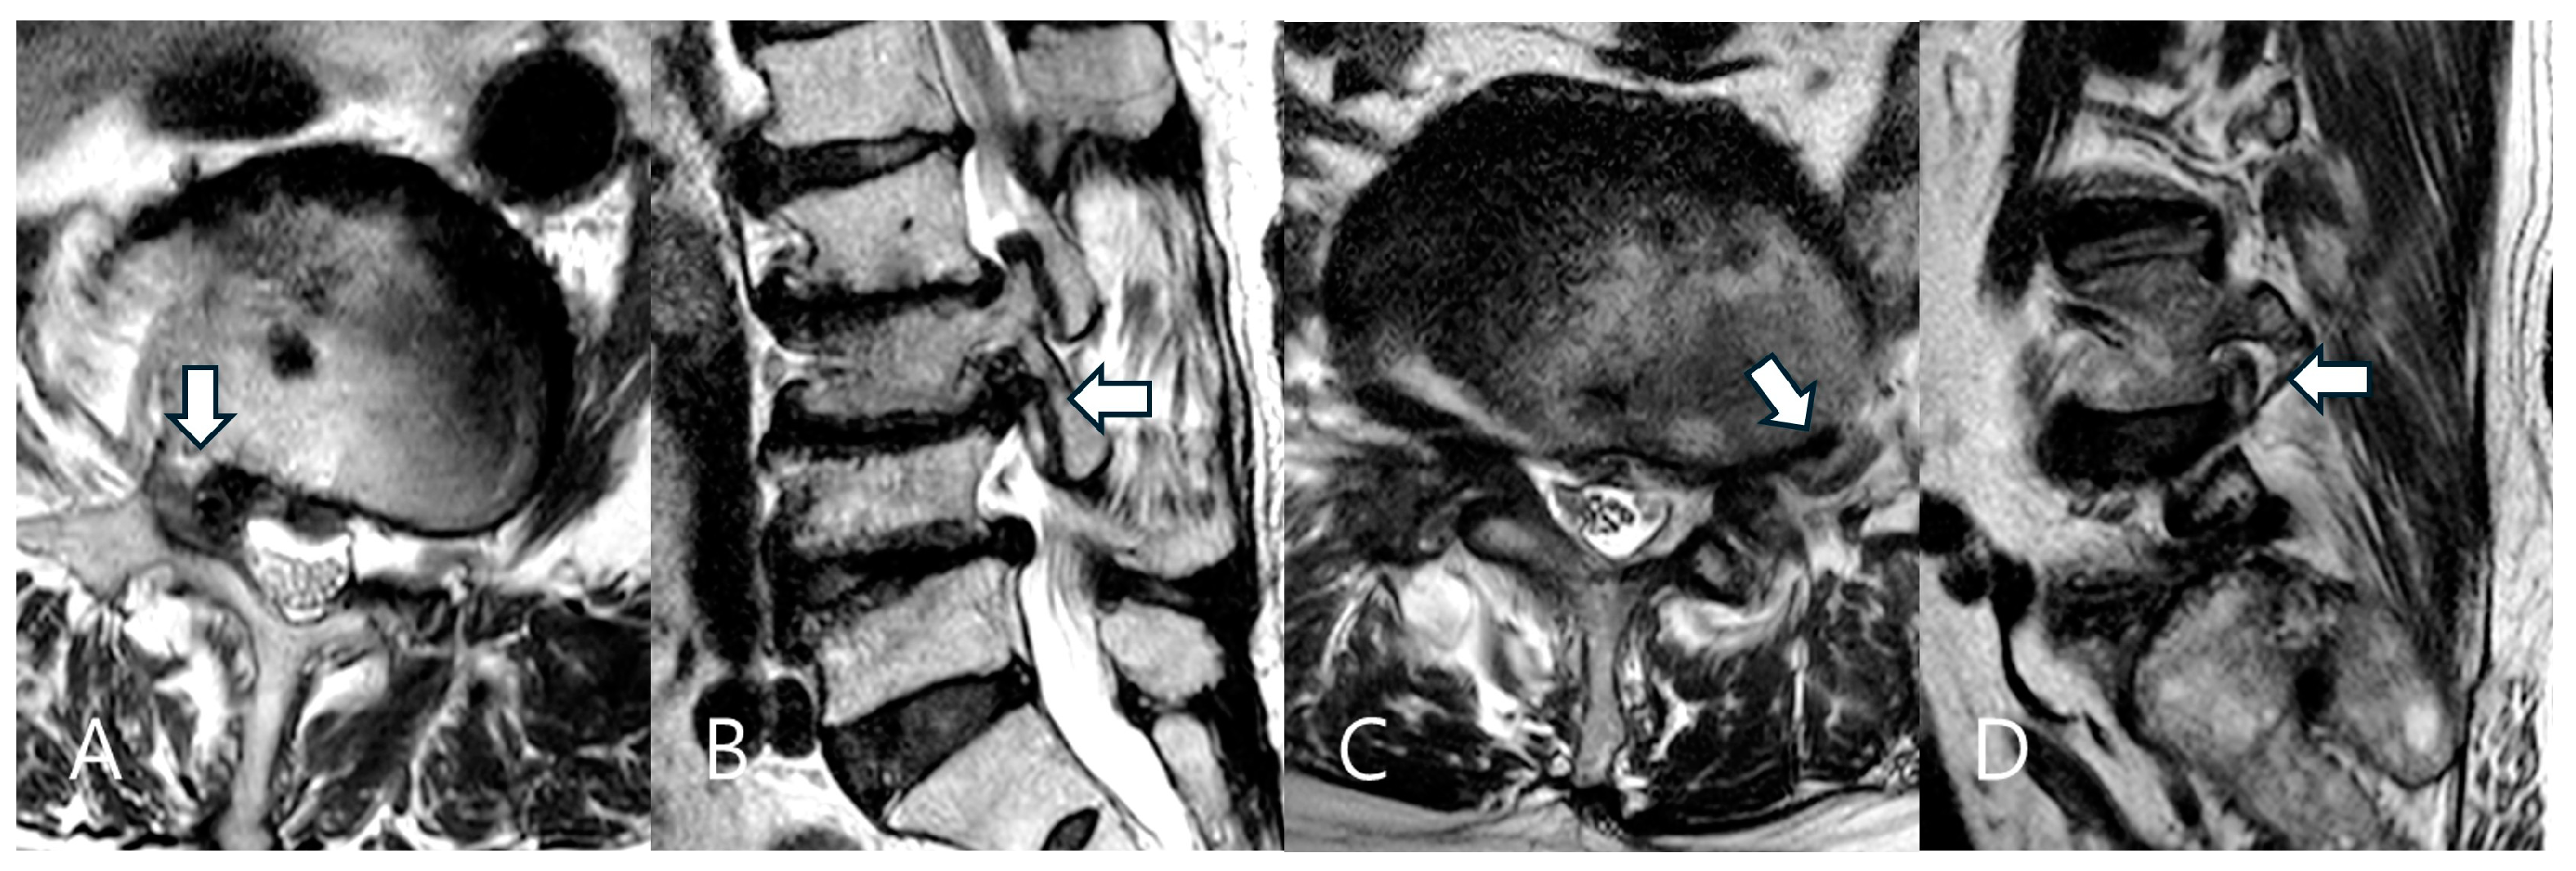

4.2. Impact of Foraminal Stenosis Grade on Perioperative Data

- Lee, S.; Lee, J.W.; Yeom, J.S.; Kim, K.J.; Kim, H.J.; Chung, S.K.; Kang, H.S. A practical MRI grading system for lumbar foraminal stenosis. Am. J. Roentgenol. 2010, 194, 1095–1098. [Google Scholar] [CrossRef]

- Park, H.J.; Kim, S.S.; Lee, S.Y.; Park, N.H.; Rho, M.H.; Hong, H.P.; Kwag, H.J.; Kook, S.H.; Choi, S.H. Clinical correlation of a new MR imaging method for assessing lumbar foraminal stenosis. Am. J. Neuroradiol. 2012, 33, 818–822. [Google Scholar]

| Grade (foraminal narrowing) | 1 | 8 | 10.7% |

| 2 | 26 | 34.7% | |

| 3 | 41 | 54.6% | |